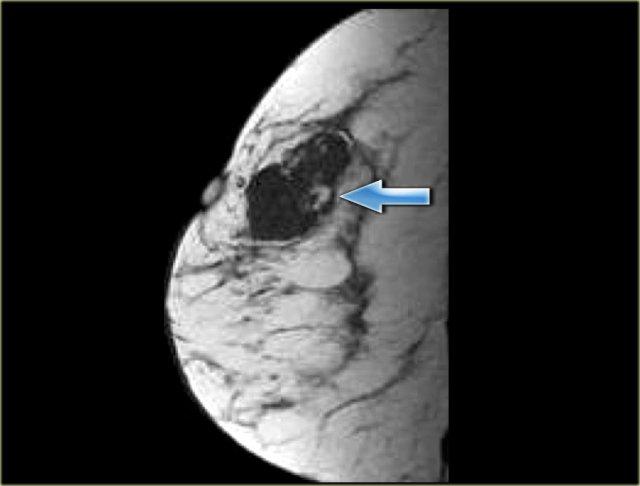

Hình ảnh ngoài cùng bên trái cho thấy một khối kèm theo ngấm thuốc theo ống tuyến xuất phát từ khối,

tương ứng với sự lan rộng ra trước và ra sau của khối u trong trường hợp DCIS này.

Hình ảnh kế bên cho thấy ví dụ về ngấm thuốc không tạo khối dạng tuyến tính theo hướng khác với hướng của các ống tuyến trong xơ hóa mô đệm.